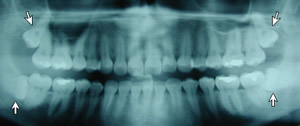

This panoramic x-ray shows

the impacted 3rd molars (wisdom teeth).

The upper wisdom teeth are crowding the sinus cavity and

may erode the roots of the 2nd molars. The lower wisdom

teeth are impacted sideways and are likely to cause crowding

of the lower teeth, leading to malocclusion.